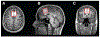

Objective: We investigated the effect of aging and cerebrospinal fluid (CSF) levels of Aβ1-42 and tau on frontal metabolites measured with proton magnetic resonance spectroscopy (MRS) in a cohort of cognitively normal older women and women with MCI.

Methods: 3T single-voxel MRS was performed on the medial frontal cortex, using Point Resolved Spectroscopy (PRESS) and Mescher-Garwood Point Resolved Spectroscopy (MEGA-PRESS) in 120 women (age range 50-85). CSF samples of Aβ1-42 and tau and scores of general cognition were also obtained.